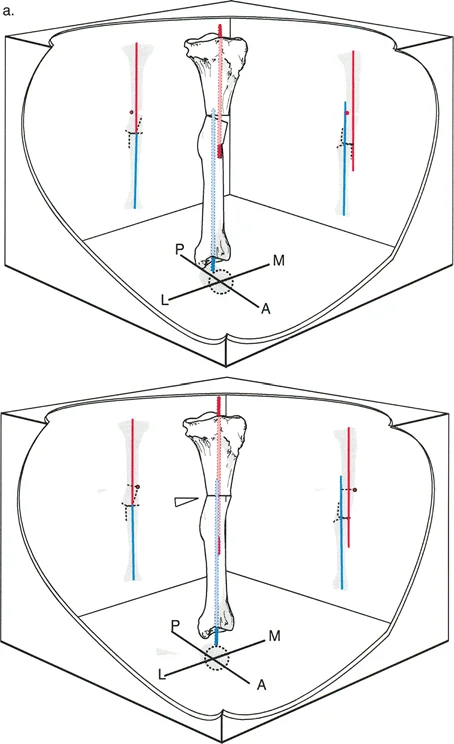

زاوية الكاحل الظهرية الظنبوبية (ADTA)

تُستخدم زاوية الكاحل الظهرية الظنبوبية (ADTA) كمعيار تشخيصي مهم لتقييم مدى تقوس الكاحل. وهي تقيس الزاوية بين محور عظم الظنبوب ومستوى عظم الكاحل. في الوضع الطبيعي، تسمح هذه الزاوية بحركة كافية لثني القدم للأعلى. أي انحراف عن هذه الزاوية الطبيعية يمكن أن يشير إلى وجود تقوس أو تشوه.

- قياس نطاق الحركة (Range of Motion): تقييم قدرة الكاحل والقدم على الثني للأعلى والأسفل، والقلب للداخل والخارج. يتم قياس زاوية الكاحل الظهرية الظنبوبية (ADTA) لتحديد درجة تقوس الكاحل.

- تساعد في قياس الزوايا المختلفة، مثل ADTA، لتحديد درجة تقوس الكاحل.